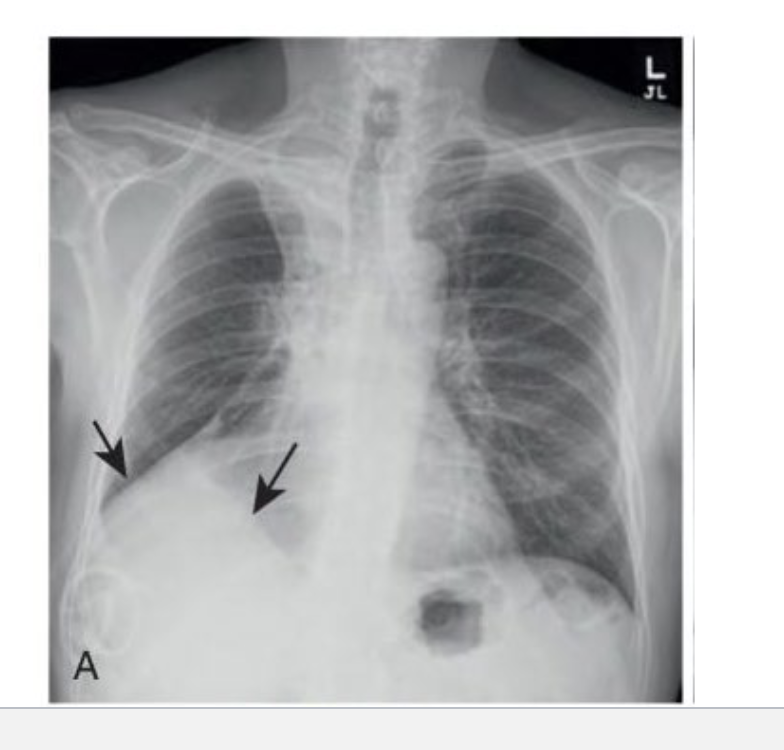

what does hemothorax look like in an CXR?

since there is blood in the thorax that may be from trauma, see a density increase on the affected side of the chest x-ray, often appearing as a concave upper border of the fluid level. might be due to chest tubes